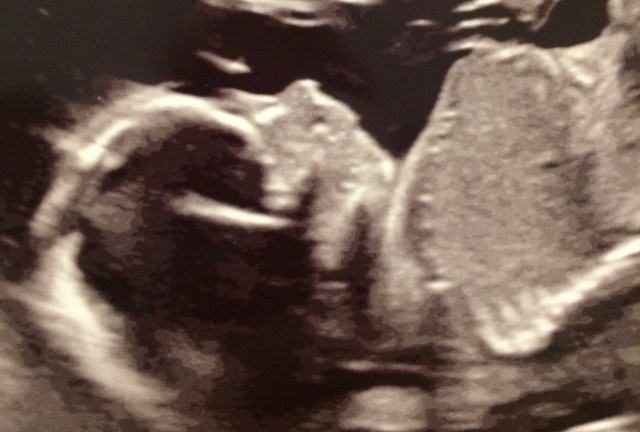

All of that trauma from Grace’s pregnancy and infancy seems so distant, and yet so fresh still in our minds. Even though everything has gone perfectly with Elliot’s pregnancy and all signs show that he’s totally healthy, I can’t help but worry. It was hard to be excited about the mid-pregnancy ultrasound until the tech assured me that everything was completely normal – even his kidneys. I find that the only thing that reassures me is hearing his heartbeat once a month at our regular midwife appointments. For those few moments, I can breathe easy – I know he’s okay. But the in-between is painful; I can’t shake the worry that maybe they missed something, maybe there is something wrong, maybe maybe maybe.